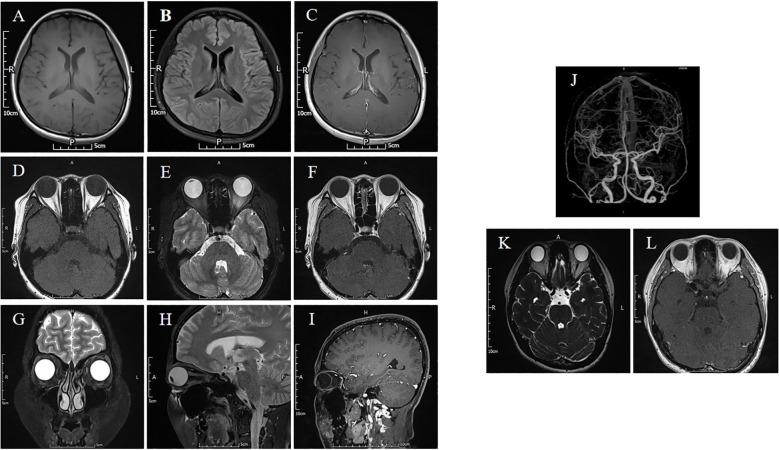

Each patient exhibited symptoms akin to extraocular myasthenia gravis (MG), with two individuals reporting diplopia and two experiencing ptosis. GAD65 antibodies were detected in either the serum or CSF, which were shown to bind with monkey cerebellum slides and mouse muscle slides. Neuroimaging of the brain and extraocular muscles via MRI showed no abnormalities, and all patients tested negative for the neostigmine test, RNS EMG, and the presence of MG antibodies. However, thyroid-related antibodies were found to be abnormal in four of the patients.